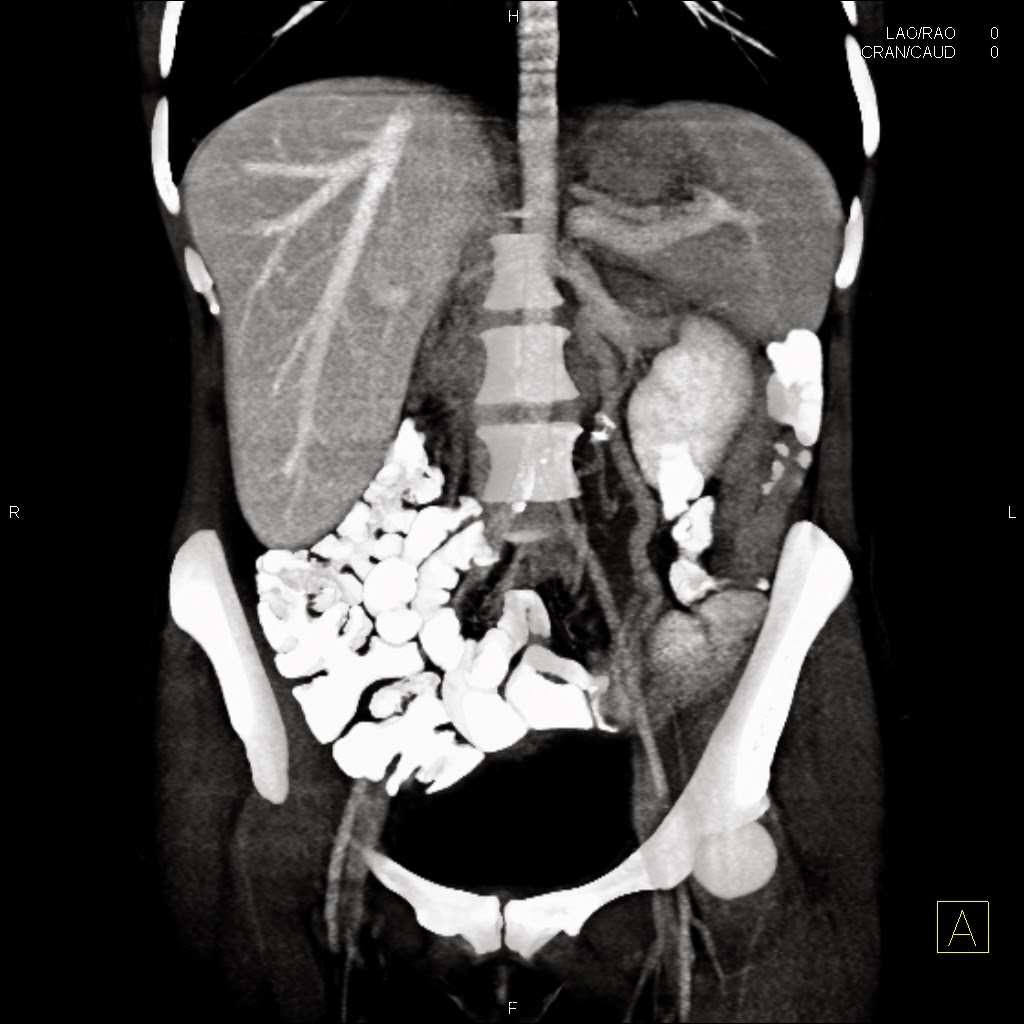

| Dilated left ovarian vein on coronal reconstruction. |

Compression of the left renal vein by the superior mesenteric artery and aorta.